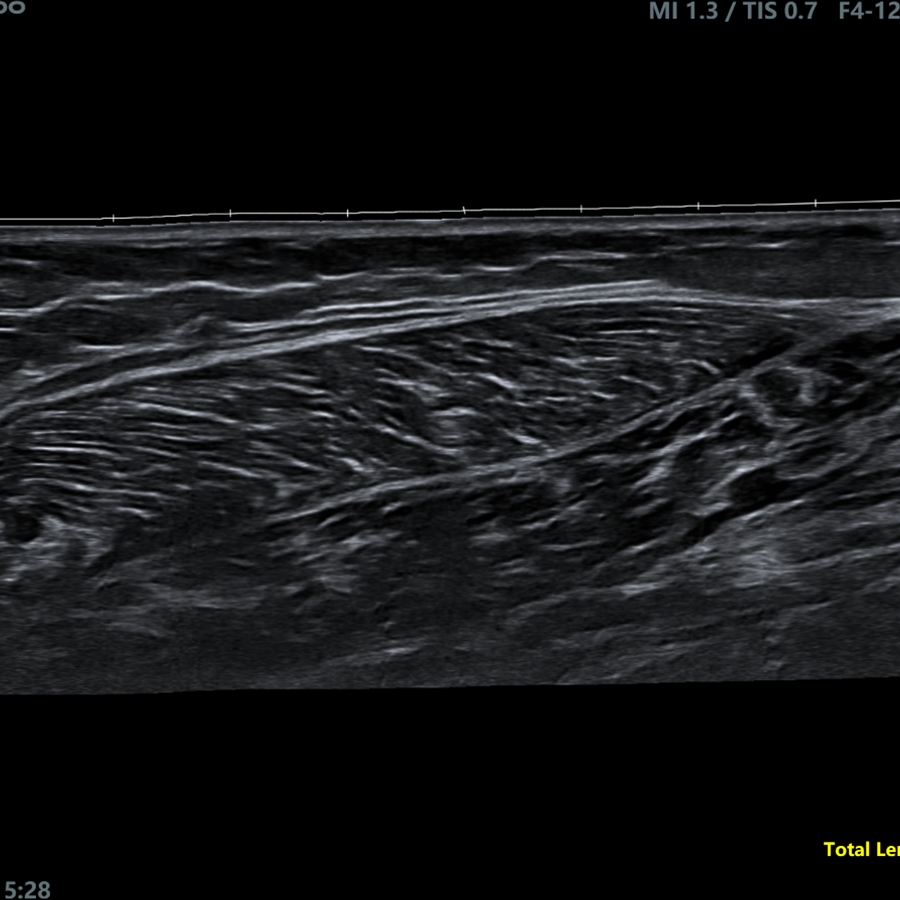

Radiología

- Elastografía Semicuantitativa

- IMT Automática

- IMT en Tiempo Real